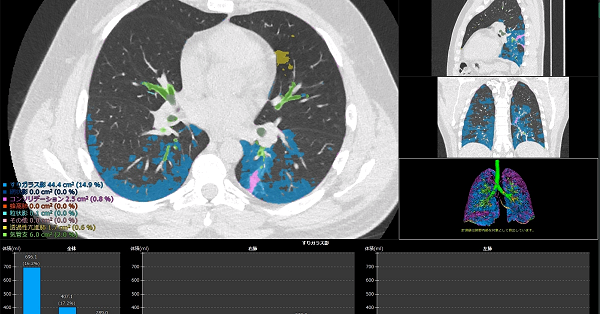

肺炎の画像診断と最新の診療 新型コロナ/富士フイルム、AIで肺炎診断支援 技術開発の詳細情報

新型コロナ/富士フイルム、AIで肺炎診断支援 技術開発。解答・解説】1カ月続く乾性咳嗽を主訴に受診した60歳代女性。肺CT検診 | JR仙台病院。肺がんの診断、特にCTとPET 豊田 尚之 - YouTube。「肺炎の画像診断と最新の診療」藤田次郎定価: ¥ 12,540#藤田次郎 #本 #BOOK #健康 #医学